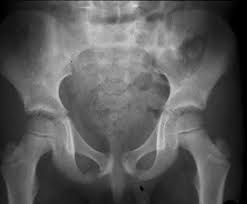

Van neck odelberg disease. Van Neck disease VND is a benign skeletal abnormality of children involving a hyperostosis of the ischiopubic synchondrosis IPS seen on radiographs. BACKGROUND Van Neck disease VND is a benign skeletal abnormality of children involving a hyperostosis of the ischiopubic synchondrosis IPS seen on radiographs. Odelberg disease - Synonym s.

The different characteristics by images from simple radiography computed tomography MRI and bone. Van Neck-Odelberg disease is a benign process that develops in children between the ages of 4 and 16 years. Van Neck-Odelberg disease or ischiopubic osteochondritis is a rare cause of pain in the pediatric pelvis due to late closure in synchondrosis ischiopubic whose main symptom is an asymmetric pain that can cause a limitation in movement or limp.

Its radiological features may mimic stress fracture neoplasm osteomyelitis or posttraumatic osteolysis. Differential diagnosis such as stress fractures osteomyelitis tuberculosis post-traumatic osteolysis or any neoplasia is need be ruled out to arrive at diagnosis. Medical Eponyms Farlex 2012.

The synchondrosis ischiopubic SIP is the cartilaginous union between the lower ischium and pubis branch in infancy. BACKGROUND Van Neck disease VND is a benign skeletal abnormality of children involving a hyperostosis of the ischiopubic synchondrosis IPS seen on radiographs. Van Neck-Odelberg disease is a syndrome characterized by an atypical ossification pattern of the ischiopubic synchondrosis. The van Neck-Odelberg disease is hyperostosis of ischiopubic synchondrosis IPS. Der Morbus van Neck oder Morbus Odelberg-van Neck ist eine seltene Form der aseptische Knochennekrose im Bereich des Beckens Synchondrosis oder Osteochondrosis ischiopubica. In van Neck-Odelberg disease an enlarged anatomical structure called ischiopubic synchondrosis is susceptible. However the radiological findings corresponded instead to van NeckOdelberg diseasea rare benign aseptic bony necrosis of the ischiopubic.